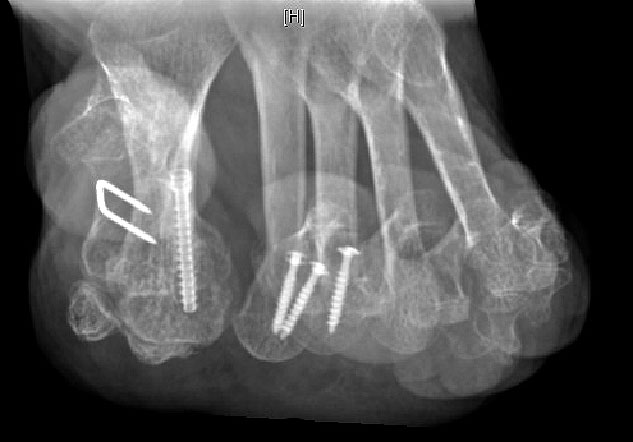

Arthrodese MTP I und weichteilige Rezentrierung MTP II und III (eigenes Bildmaterial)

Abbildung 18

Gute Ergebnisse werden in diesem Fall durch die Arthrodese des MTP-1-Gelenkes erzielt. Bei älteren Patienten kann zum Erhalt der Beweglichkeit eine Keller-Brandes-Prozedur sinnvoll 2327, (Wirth, 2002)